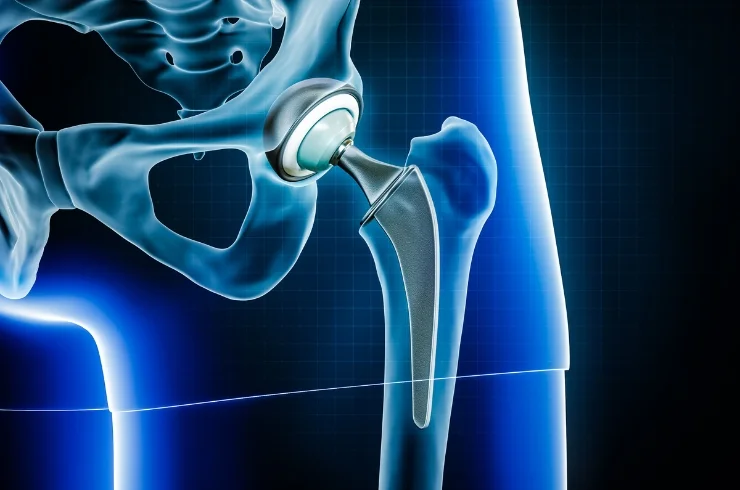

Dr. Manal Gore is a highly skilled Consultant Orthopaedic Surgeon specializing in the diagnosis and treatment of musculoskeletal disorders. With expertise in Robotic & Conventional Joint Replacement, Complex Trauma Surgery, Arthroscopy & Sports Medicine, Minimally Invasive Procedures, and Osteoarticular Infection Management, Dr. Gore provides comprehensive orthopaedic care for patients of all ages.

With a strong focus on evidence-based medicine, Dr. Gore is committed to delivering personalized treatment plans that ensure faster recovery, improved mobility, and long-term outcomes. His clinical approach combines advanced surgical techniques with non-surgical care, helping patients return safely to their daily activities, sports, and pain-free movement with confidence.